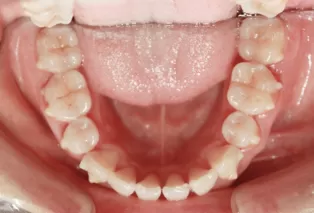

Photos intra-orales